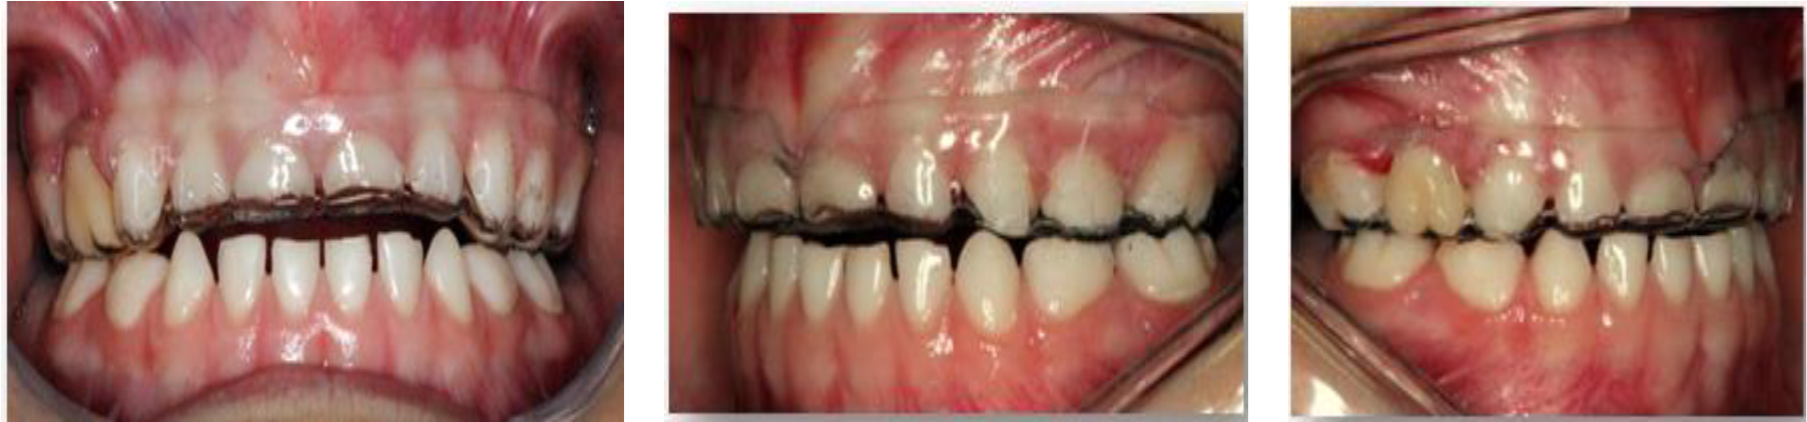

Figura 14. Ajuste oclusal bilateral para establecer puntos de contactos estables y equilibrados. Después de realizar los controles oclusales y la instalación de la placa se realizaron controles pos-instalación a los 15,30,60 y 90 días.

Así como, Solanki (Sakai, et al., 2017) menciona que el tratamiento de pacientes bruxistas debe basarse en aliviar los síntomas y proteger al sistema estomatognático, a través de férulas o placas interoclusales que permiten relajar los músculos tensionados, así como evitar el desgaste de los dientes y reducir el dolor de los músculos masticatorios. Este caso clínico, está en concordancia con los resultados encontrados por Lobbezoo (2013) y Sakai, et al., (2017), ya que al instalar la placa interoclusal en la paciente se pudo observar como la paciente mencionaba en los controles a los 15 y 30 días, alivio de los dolores de cabeza, ausencia de dolor a la palpación de los músculos masticatorios, así como un control de los desgaste de las estructuras de los dientes a nivel incisal.